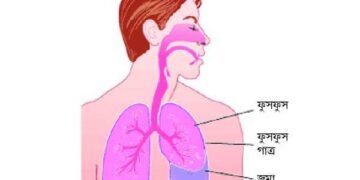

হার্টবিট ডেস্ক ফুসফুস আমাদের শরীরের গুরুত্বপূর্ণ অঙ্গগুলোর মধ্যে একটি। এর দীর্ঘমেয়াদি কিছু রোগ রয়েছে। যার মধ্যে ক্রনিক অবস্ট্রাকটিভ পালমোনারি ডিজিজ...

Read moreহার্টবিট ডেস্ক যখন কেউ এ কথা জিজ্ঞাসা করেন, আপনার উত্তরটা ‘হ্যাঁ’-ই হয়! কিন্তু, আপনার ফুসফুস? মুশকিল হল, সে বেচারার উত্তরটা...

Read moreহার্টবিট ডেস্ক আমাদের শরীরের নানা অংগের কিছু অসুস্থতা ফুসফুসের বড় ও ছোট সমস্যার ইঙ্গিত দিতে পারে যা সম্পর্কে অবহিত হয়ে...

Read moreডা. মো. জিয়াউল করিম ফুসফুস ঢেকে থাকে এক ধরনের পাতলা আবরণী বা প্লুরায়ে। এতেই পানি জমে। এ রোগের নাম প্লুরাল...